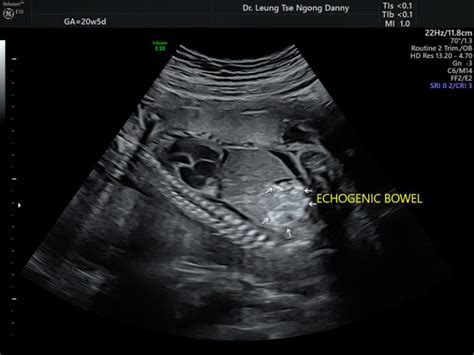

20-Week Scan: Understanding Echogenic Bowel Findings

So, let’s dive right into understanding echogenic bowel , a term that often causes a little flutter of anxiety when it’s mentioned after a 20-week ultrasound. Simply put, when an ultrasound technologist or doctor says a baby has echogenic bowel , they’re referring to a specific appearance of the baby’s intestines on the ultrasound screen. “Echogenic” means it appears brighter, or whiter, than what’s typically expected for a fetal bowel. Think of it like this: on an ultrasound, different tissues reflect sound waves differently, creating varying shades of grey, black, and white. Bone, for instance, is very echogenic and appears bright white. Normally, a baby’s intestines during the 20-week anatomy scan should look similar in brightness to the liver, which is a medium grey. If the intestines appear as bright as, or even brighter than, the surrounding bone structure, then it’s classified as echogenic bowel . It’s a visual observation, not a direct diagnosis of a specific condition itself, but rather a marker that prompts further investigation. This particular finding occurs in about 0.2% to 1.8% of all pregnancies, which means while it’s not super common, it’s also not unheard of. The reason for this increased brightness can vary widely. Sometimes, it’s due to the presence of blood in the fetal gut, which could be from a small bleed. Other times, it might be due to a thicker-than-normal meconium (the baby’s first stool) because of a lack of fluid. Occasionally, it could signify some calcification or a slight increase in tissue density within the bowel. The key takeaway here is that echogenic bowel is a finding that needs context. It’s like a red flag that says, “Hey, let’s take a closer look,” rather than an immediate alarm bell. The excellent news is that in a significant number of cases, perhaps even the majority, an isolated finding of echogenic bowel, meaning there are no other unusual findings on the scan, resolves on its own or turns out to be entirely benign, with the baby being perfectly healthy at birth. This is why getting comprehensive information and follow-up care is absolutely paramount. Don’t jump to conclusions, guys; let the experts guide you through the next steps, which are designed to give you peace of mind and the best possible care for your little one.